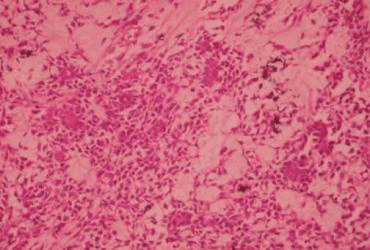

হিস্টোপ্যাথলজি নরম টিস্যুতে একাধিক সীমাবদ্ধ নোডুলার ক্ষত হিসাবে রিপোর্ট করেছে। এগুলিকে ছেদকারী কর্ড এবং ট্র্যাবেকুলাতে বিক্ষিপ্ত বহুভুজ কোষের সাথে মাইক্সয়েড লুকিং স্ট্রোমার তুলনা করা হয়। কোষের গোলাকার থেকে ডিম্বাকৃতির ব্লান্ড নিউক্লিয়াস থাকে। মাইটোসিস, নিউক্লিয়ার অ্যাটাইপিয়া দেখা যায় না। ভাস্কুলার টিউমার এম্বলি দেখা যায় না। ছাপ ছিল Pleomorphic Adenoma এর দাগ সাইট পুনরাবৃত্তি.

"Pleomorphic" শব্দটি টিউমারের হিস্টোজেনেসিস এবং হিস্টোলজি উভয়কেই বোঝায়। 12 টিউমারের 3টি উপাদান রয়েছে: একটি এপিথেলিয়াল কোষের উপাদান; একটি myoepithelial কোষ উপাদান; এবং একটি স্ট্রোমাল (মেসেনকাইমাল) উপাদান। এই 3 টি উপাদানের সনাক্তকরণ, যা একটি টিউমার থেকে অন্য টিউমারে পরিমাণগতভাবে পরিবর্তিত হতে পারে, প্লোমোরফিক অ্যাডেনোমার স্বীকৃতির জন্য অপরিহার্য। প্লিওমরফিক অ্যাডেনোমা নির্ণয়ের জন্য ফাইন-নিডেল অ্যাসপিরেশন বায়োপসি করা যেতে পারে। 13 হিস্টোলজিক্যালি প্লিওমরফিক অ্যাডেনোমা একটি ঢিলেঢালা তন্তুযুক্ত স্ট্রোমাতে এপিথেলিয়ামের পরিবর্তনশীল প্যাটার্নের সাথে উপস্থাপন করে, যা মাইক্সয়েড, কনড্রয়েড বা মিউকয়েড হতে পারে। এপিথেলিয়াম সাধারণত শীট বা স্ট্র্যান্ডে সাজানো হয় এবং নালীর গঠন, প্রায়শই দ্বিস্তরযুক্ত, অ্যাটিপিকাল হয়। মায়োপিথেলিয়াল কোষগুলি প্রায়শই ফ্যাকাশে ইওসিনোফিলিক সাইটোপ্লাজম সহ বহুভুজ হয়।

প্লিওমরফিক অ্যাডেনোমাসের মাইক্সয়েড স্ট্রোমা এটির অন্যতম বৈশিষ্ট্যযুক্ত বৈশিষ্ট্য। এটি টিউমারের প্রধান অংশ গঠন করতে পারে এবং কোন ক্যাপসুলের হস্তক্ষেপ ছাড়াই স্বাভাবিক গ্রন্থি প্যারেনকাইমাতে ফুলে যেতে পারে।